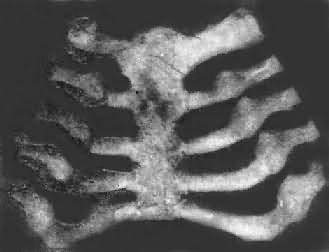

肋骨和肋软骨结合处的改变与长骨骺板及干骺端的改变相似,由于软骨及骨样组织的堆积,致使肋骨和肋软骨的结合部呈结节状隆起。因多个肋骨同时受累,故结节状隆起排列成行,形似串珠,称为佝偻病串珠(rachitic rosary)(图17-11),常是佝偻病的较早期表现之一。此外,肋骨因含钙量少,缺乏韧性,同时由于膈在呼吸时的长期牵拉,在胸壁前部左右两侧各形成横行的沟形凹陷,称为Harrison沟。又因在呼吸时,肋骨受肋间肌的牵拉而下陷,使胸骨相对向前突出,形成鸡胸畸形。

佝偻病的肋骨

图17-11 佝偻病的肋骨

肋骨和肋软骨结合部呈结节状隆起,排列成行,形似串珠